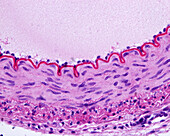

13416586 - Aorta tunica media and adventitia, light micrograph

12634941 - Aorta, tunica adventitia and media, LM

12634940 - Aorta, tunica adventitia and media, LM

12634939 - Aorta, tunica adventitia and media, LM